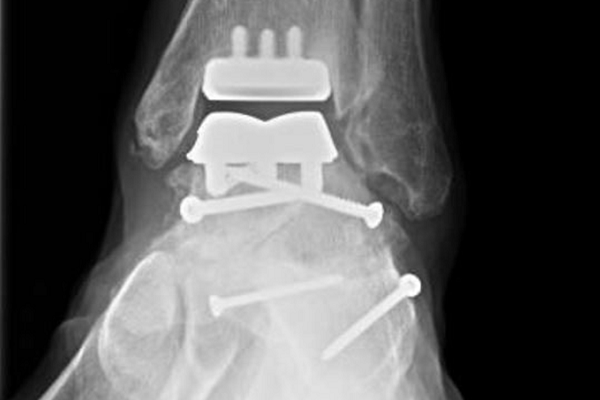

“We go through the front of the ankle to see the entire joint. I remove bone and cartilage. Then we put in the artificial implant made of metal,” said Dr. Brohard. “In between the two pieces of metal there is plastic that works like a hinge, so you still have all the ligaments and tendons around the ankle.”

The orthopedic surgeon said currently the technology lasts about 10 to 15 years before revision is needed. Emry was only 52 when Dr. Brohard replaced his ankle.